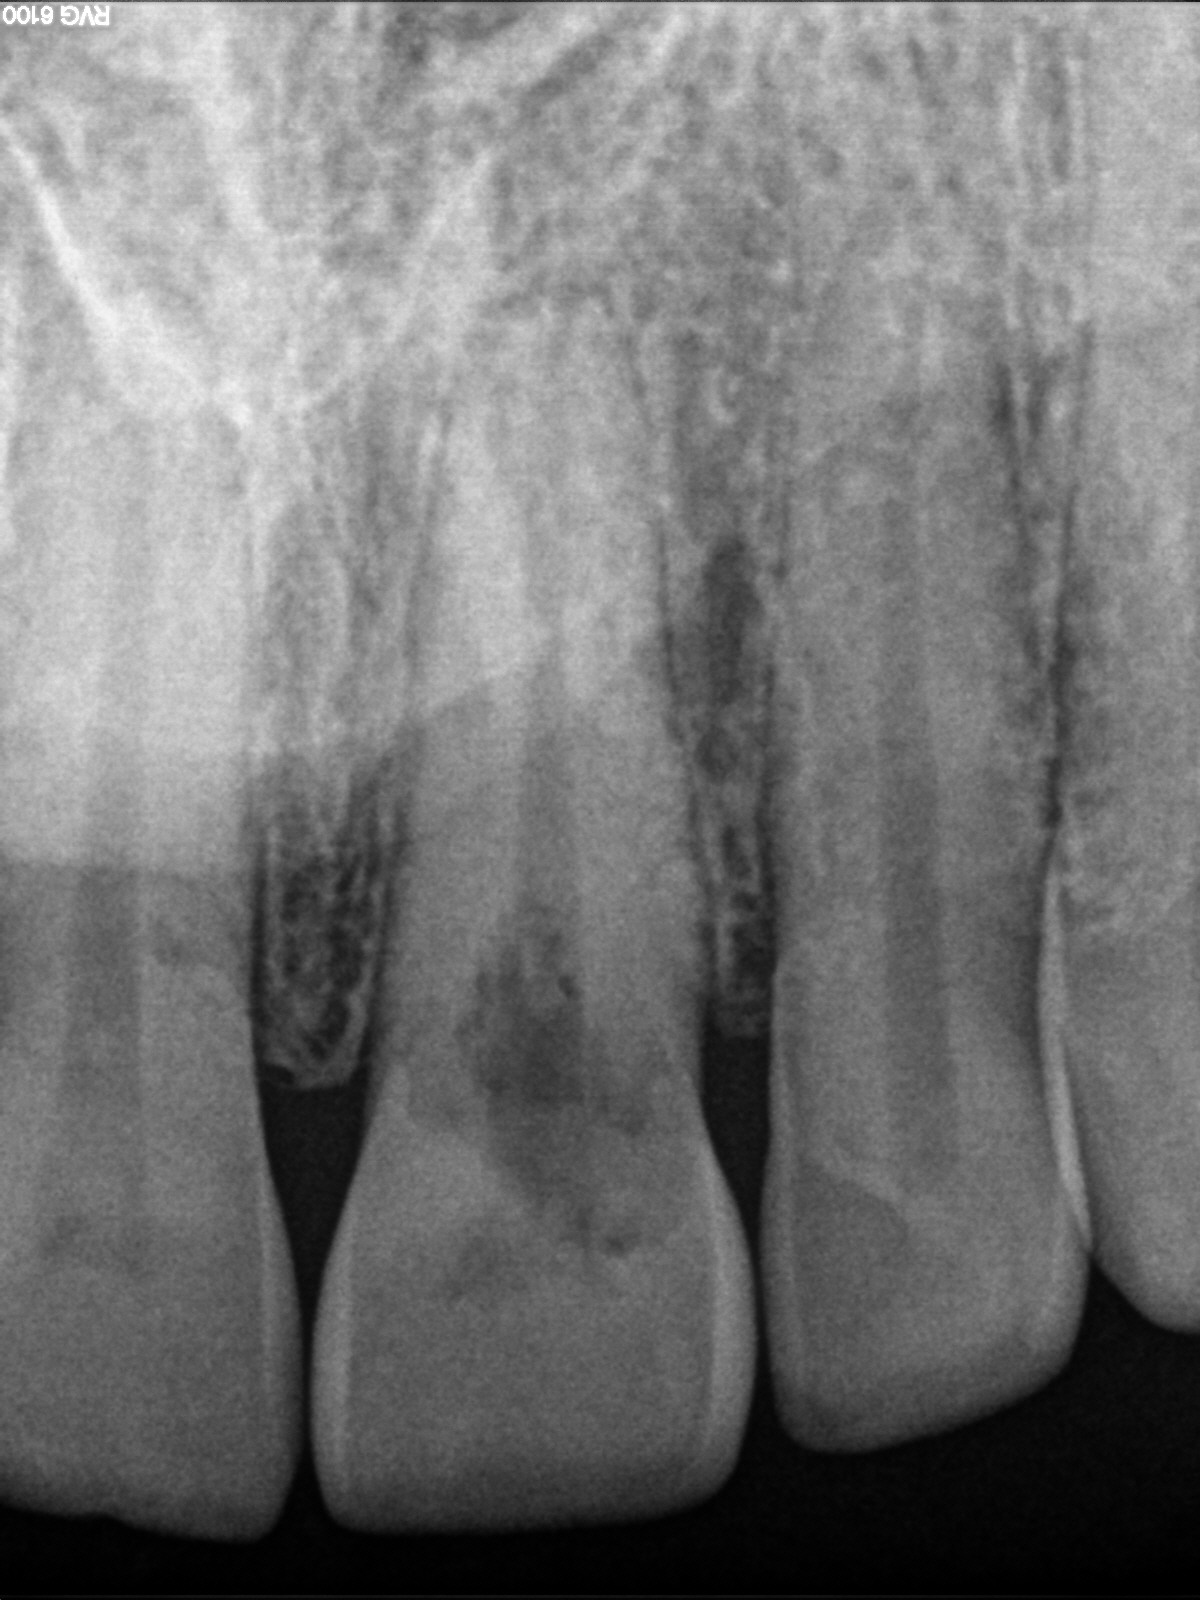

R1

Back to the Future